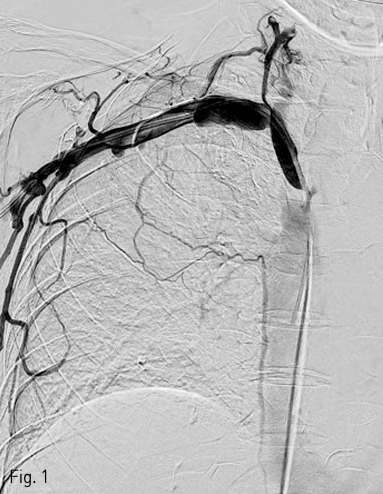

국소 마취를 시행하고 우측 대퇴정맥을 천자하여 0.035 인치 유도 철사 (Terumo, Tokyo, Japan) 와 5F C2 catheter (Cook, Bloomington, IN) 를 이용하여 catheter를 우측 쇄골하정맥에 위치시키고 시행한 정맥조영술에서 상대정맥의 협착을 확인하였다 (Fig. 1). 0.035 인치 유도철사를 따라 직경 10mm, 길이 4cm sized balloon catheter (ATB advance; Cook, Bloomington, IN) 를 삽입하여 상대정맥의 협착부위에 대해 풍선 확장술을 시행하였다 (Fig. 2). 10mm balloon으로 확장 중 waist가 발생하였으며 6 atm 시 waist가 소실되었다 (nominal pressure 5 atm, burst pressure 14 atm). 풍선 확장술 시행 후 시행한 정맥조영술에서 상대정맥에 조영제 유출과 우측 폐에 혈흉이 관찰되었다 (Fig. 3A, B). 이에 즉시 0.035 인치 유도철사를 따라 직경 10mm balloon catheter를 다시 삽입하여 조영제 유출 부위에 대해 balloon tamponade를 시행하였다. Balloon tamponade 후 시행한 정맥 조영술에서 조영제 유출의 양은 감소하였으나 지속적인 조영제 유출이 관찰되어 0.035 인치 유도철사를 따라 직경 14mm, 길이 6cm sized Wallstent (Boston scientific, Natric, MA)를 조영제 유출 부위에 설치하였다. 시술 후 시행한 정맥조영술에서 스텐트를 통한 혈류의 흐름이 원활하고 더 이상 조영제 유출이 되지 않는 것을 확인하였다 (Fig. 4). 혈흉의 치료를 위해 10.2F drainage catheter (Cook) 를 우측 흉강에 설치하였다.

Fig 1

Right subclavian venogram shows near-total obstruction of superior vena cava with collateral vessels.